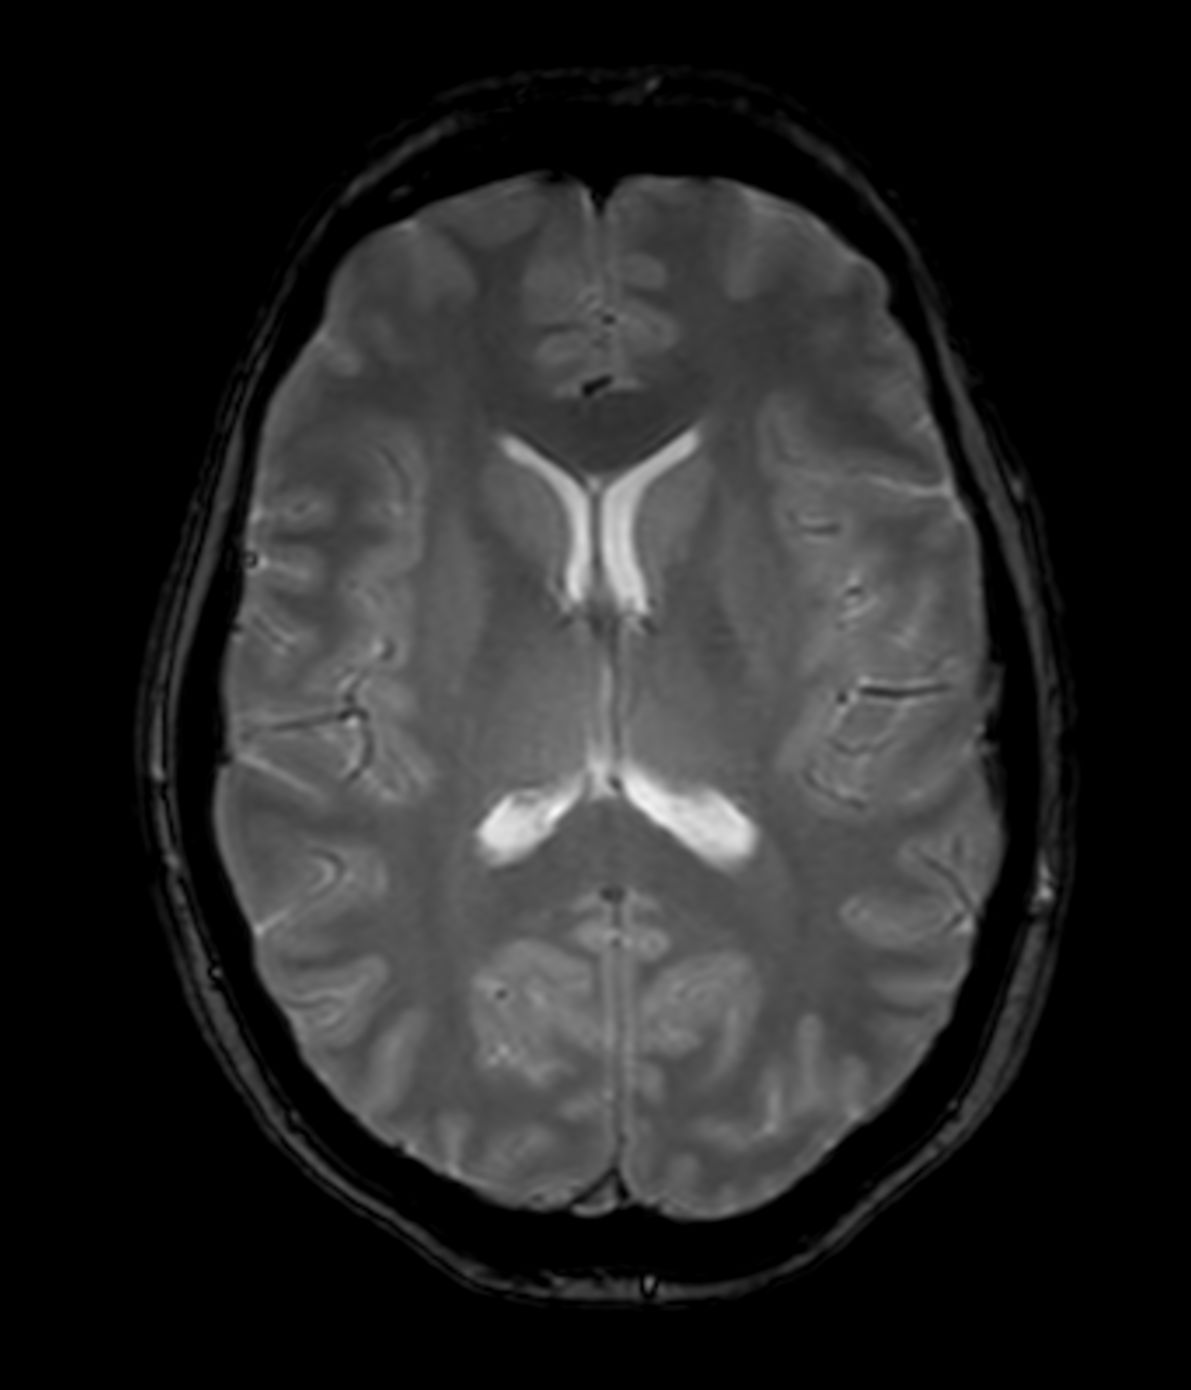

Alzheimer’s Disease Anti-Amyloid Immunotherapies (ARIA) 3.0T

Amyloid clearing medication, such as Aduhelm (Aducanumab) and Leqembi (Lecanemab) have been cleared by the FDA in 2022/2023, to slow down cognitive decline in early-stage Alzheimer’s disease. ASNR-recommendations for AD therapeutic imaging were published in 2022 for eligibility assessment as well as for monitoring for amyloid-related imaging abnormalities. This ExamCard includes ASNR-recommended consensus protocols for imaging of Alzheimer’s Disease Anti-Amyloid Immunotherapies (ARIA). (Cogswell et al., AJNR 2022,43(9)E19-E35;DOI: https://doi.org/10.3174/ajnr.A7586))